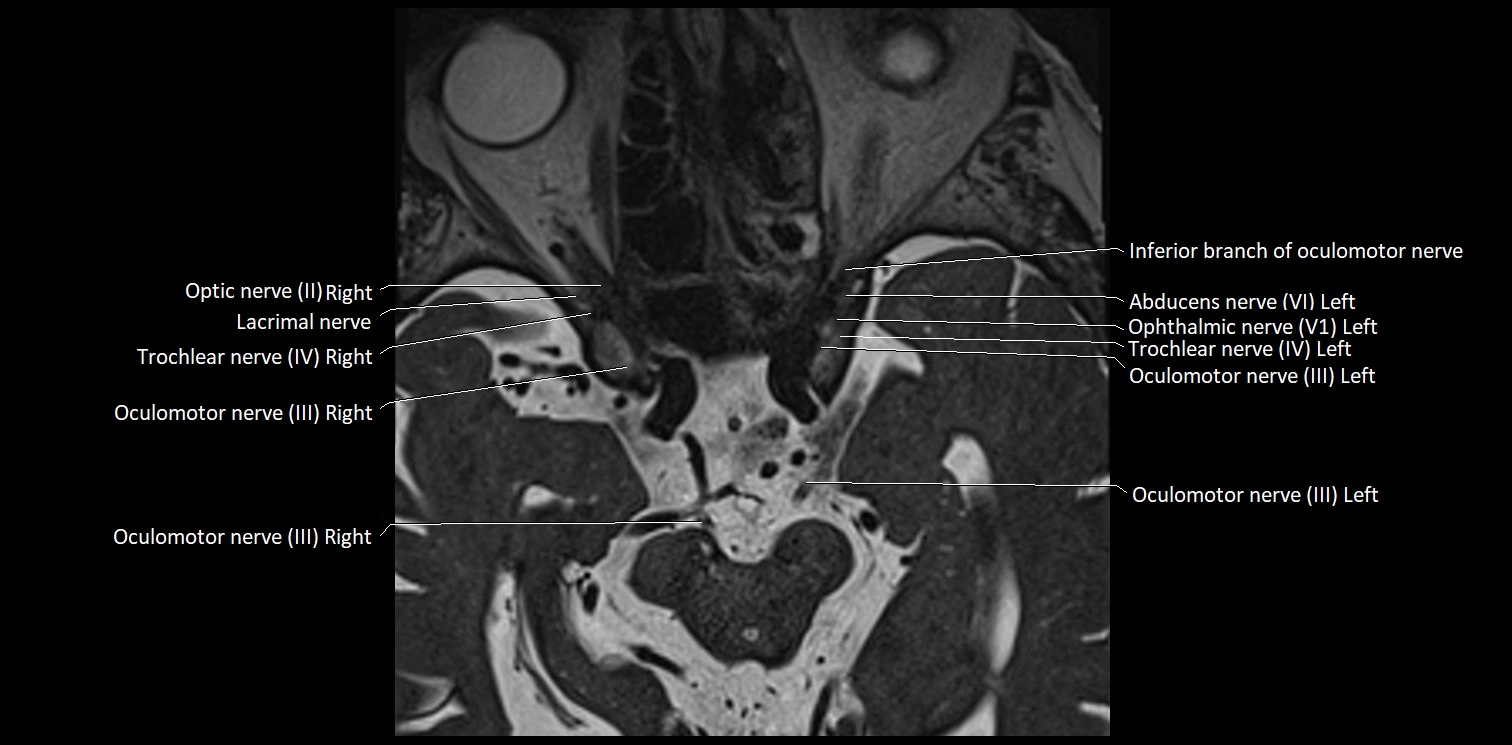

MRI Appearance

• The abducens nerve is a small, thin, linear structure

• Best visualized on high-resolution T2-weighted 3D MRI sequences (e.g., FIESTA or CISS)

• Seen as a hypointense (dark) line running from the brainstem at the pontomedullary junction, traversing the prepontine cistern, and entering Dorello’s canal under the petrosphenoidal ligament, then into the cavernous sinus, and finally the orbit

• May be challenging to visualize in standard MRI due to its small size

• Pathology may be inferred by absence, displacement, or enhancement of the nerve

MRI images

image